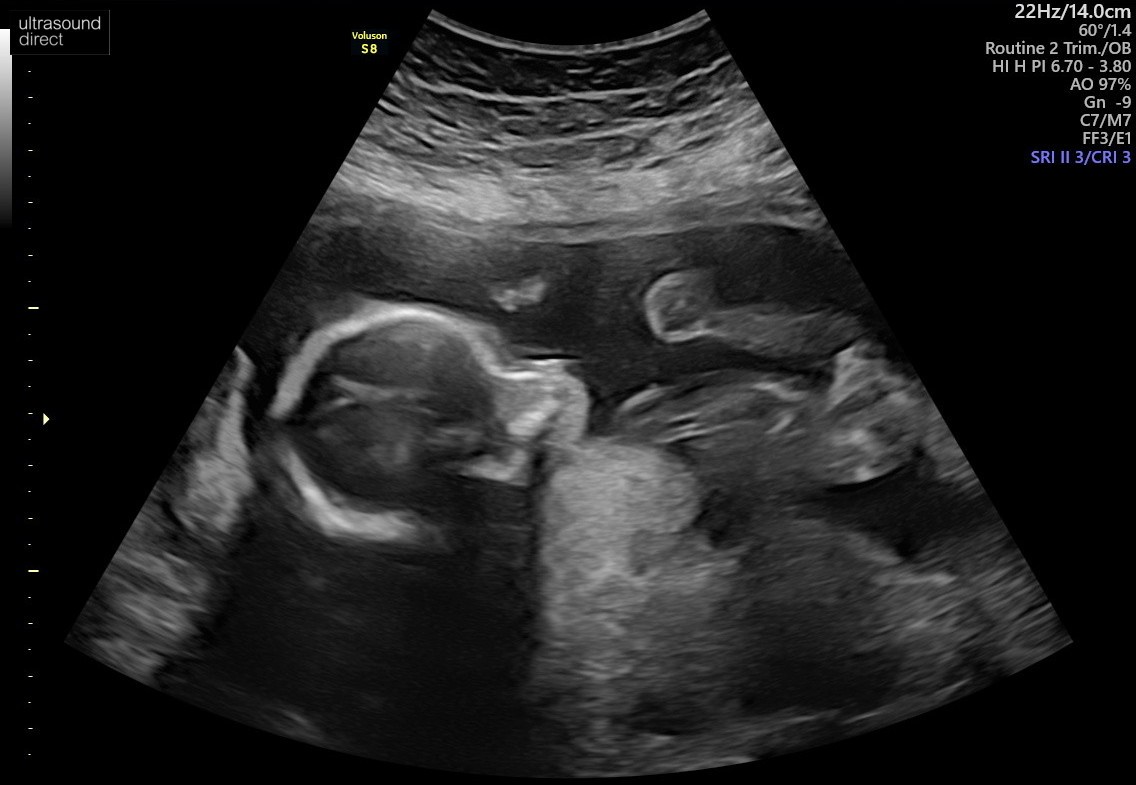

Wg mnie wygląda to na dziecko...Witajcie

Może sprawne oko którejś mamusi podpowie czy po tym rozmazanym USG można stwierdzić płeć maleństwa![]()

Nie da się stwierdzić płci po tych zdjęciach... A lekarz nic nie powiedział?Witajcie

A mi pani doktor powiedziała "dziewczynka" a pan doktor na prenatalnych "chłopiec"Wg mnie wygląda to na dziecko...

Poważnie, jak lekarz nie powiedział płci to losowe osoby z forum powiedzą.

A jak powiedział płeć to możesz mu zaufać lub powtorzyc badanie u innego specjalisty.

Wystarczy zaczekać do kolejnej wizyty i zapytać. A jak się niecierpliwisz to zadzwoń i niech sprawdzą w karcie jaka płeć.Nie chodzi tu o brak zaufania do lekarza tylko o to, że w dniu USG mamusia nie chciała znać płci dziecka.

Ciekawość jednak wzięła górę

I wiem, że lekarzami nie jesteśmy (przynajmniej w większości) więc nie ma co się spinać. Za to są tu mamy z różnym doświadczeniem i na ich opinię liczę![]()